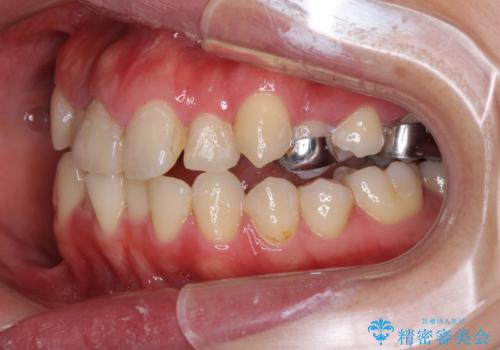

- 上下のデコボコと奥歯の咬みにくさを気にして来院された患者様です。

上顎骨の幅が下顎骨よりも小さいので、拡大装置により骨幅を広げて上下関係を改善し、その後インビザラインにて歯並びを整えることとしました。

上下の骨幅を改善したことで、スムーズに歯列矯正を行うことができました。

奥歯の咬み合わせを改善する必要があったため、治療は長期化しましたが、きっちりと仕上げることができました。